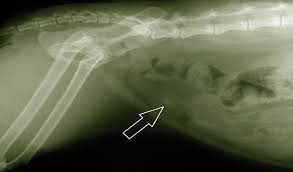

The pet may vomit, refuse food and. Struvite bladder stones or crystals (also known as triple phosphate) are the most common type of bladder stones seen in dogs and cats. Other cats with crystals or bladder stones may have blood in their urine and may urinate frequently, passing only small quantities of urine each time. Depending on the minerals that make up the stone, its shape and size will vary. September 24, 2015 comments off on bladder stones in dogs and cats.

What causes bladder stones in cats? Bladder stones are common in both dogs and cats. 3.0 bladder crystals, stones vs.kidney crystals,stones. Depending on the minerals that make up the stone, its shape and size will vary. If the cat has bladder stones, a stone, or group of stones, will be seen in the urinary bladder, or other parts of the urinary system such as the kidney use canned food instead of dry food. Many good pet food manufacturers will make a prescription diet specifically for. Some cats may not show symptoms immediately or minimal symptoms. Struvite bladder stones in cats natural treatment. Pets rarely suffer from kidney stones, but can have the more common bladder symptoms can be straining to urinate but producing little urine, bloody urine, frequent attempts at urination. However, hills science plan is a good food, the unrinary. For a cat that has stones in its bladder, what are some holistic alternatives to surgery? Bladder crystals and eventually stones usually form when a dog's or cat's bladder is not this should assist you in assessing if these foods are really appropriate to support the treatment and resolution of bladder and kidney stones as well. In this video dr jones shows you the 3 most common bladder stones in pets, along with the top 3 remedies.

If the cat has bladder stones, a stone, or group of stones, will be seen in the urinary bladder, or other parts of the urinary system such as the kidney use canned food instead of dry food.

Bladder crystals and eventually stones usually form when a dog's or cat's bladder is not this should assist you in assessing if these foods are really appropriate to support the treatment and resolution of bladder and kidney stones as well. The stones form in the urinary bladder in varying size and numbers secondary to infection. Thebarkspace.com is a participant in the amazon services llc associates program, an affiliate advertising program designed to provide a means for sites to earn advertising fees by advertising and linking to amazon.com. Blocked bladders in male cats happen when tiny bladder stones pass out the bladder down into the urethra inside the penis. Learn about bladder stones in cats including symptoms, causes, treatments, diagnosis, and more. Dry food isn't recommended, but if you must feed manufactured food you can choose from suitable wet, canned options. In some cases they can block the flow of urine, which is a medical emergency. Cats with bladder stones don't always showsymptoms, and the stones are often discovered as part of a routine exam. Signs of bladder or kidney stones in cats: If the cat has bladder stones, a stone, or group of stones, will be seen in the urinary bladder, or other parts of the urinary system such as the kidney use canned food instead of dry food. Sometimes cats will show no symptoms but things to look out for are. Your vet will prescribe the specially formulated food based on your cat's final diagnosis. Cats with bladder stones typically have some or all of the following symptoms: